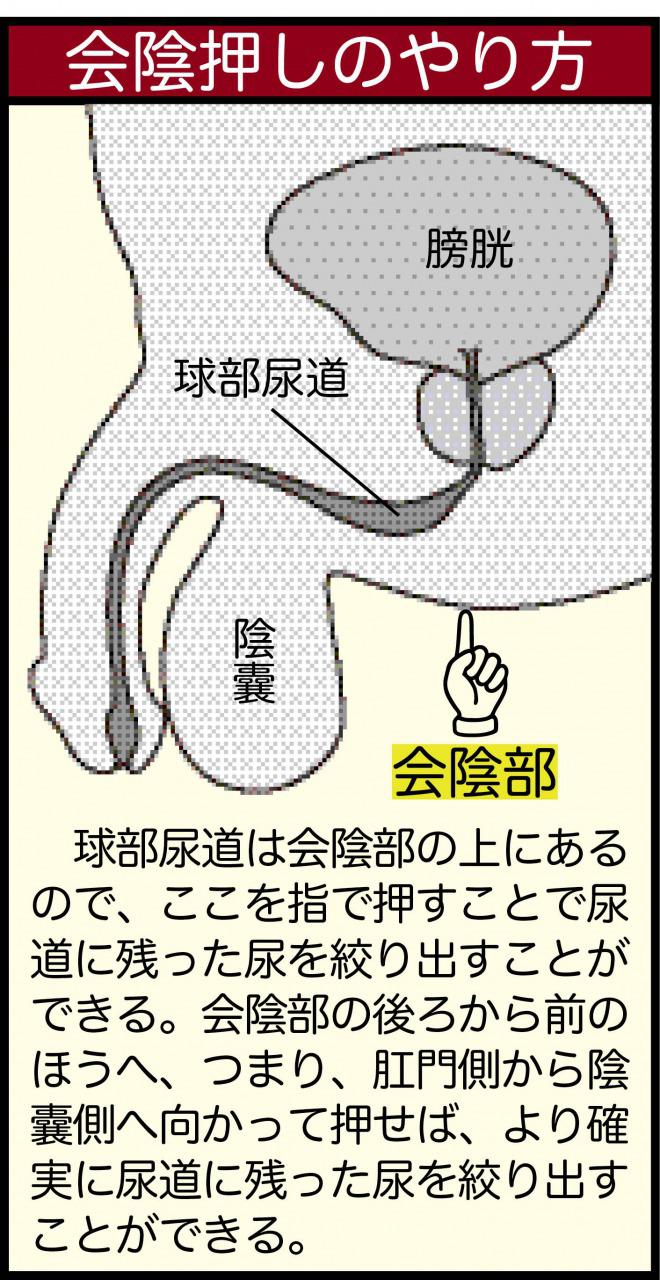

尿が垂れる その対策 男性編 こだいら泌尿器科

男の尿トラブルの主犯は前立腺肥大 ちょい漏れは会陰部指圧で解決 尿のトラブル 自力で解決 日経gooday グッデイ

尿が垂れる その対策 男性編 こだいら泌尿器科

おしっこトラブル 50代の5人に1人が悩む不快なチョイもれ 排尿後尿滴下 とは ケンカツ

尿が垂れる その対策 男性編 こだいら泌尿器科

悩ましい 残尿 に秘策はあるか ライフリー ユニ チャーム

尿漏れ男の対策 出終わったと思った後に出るときにする3つのこと 40代の中年男の情報マガジン